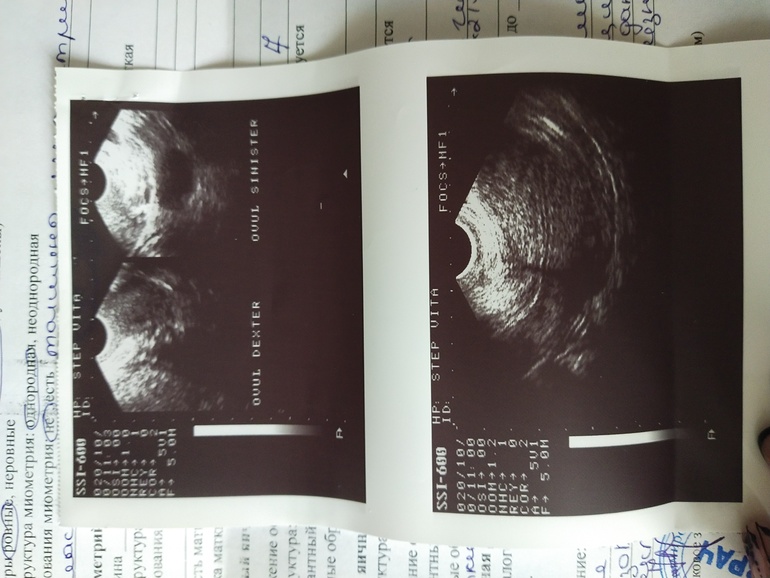

ФолликулометрияВсем привет? Активно планируем лялю только третий цикл. сегодня 8 день цикла сходила на узи я. Врач сказала, что в прошлом цикле была киста жёлтого тела, и она ещё не вышла. Дм фолликулов нет.и овуляции в этом цикле не будет. Вопрос такой, мне мой врач прописала Дюфастон с 16 по 26 день цикла. Как думаете что в этом цикле делать? Пить его или нет? Узист сказала смысла ещё раз делать в этом цикле узи нет.